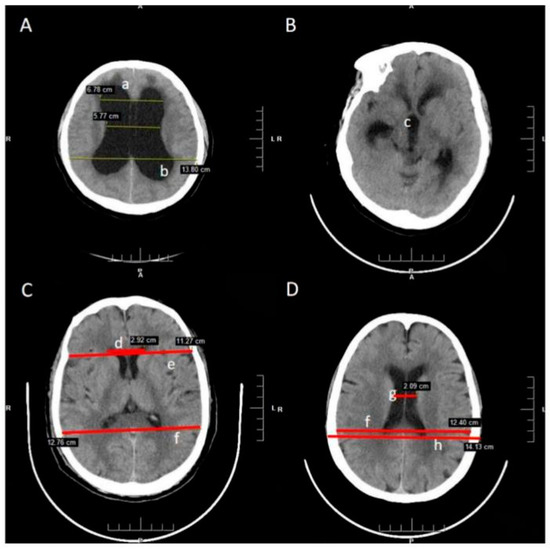

All images were taken by a trained and experienced neuroradiologist and clinician in standardized condition and manner. Although the diagnostic value of MRI is irreplaceable, CT images, the preferred measurement of the parameters in practice, are more popular and convenient in the clinic. All patients had examination of the brain using the department’s Siemens 298 slice Somatom definition AS multi-detector spiral CT. Based on the measurements following linear indices were calculated [14,15]. All the measures used in the calculation of parameters are demonstrated in Table 1 and Figure 1 [16,17].

Table 1. The Radiological Features and Morphometric Parameters of CT Image.

Figure 1. Radiological features and morphometric parameters in CT image. (A). The layer of enlargement ventricle; (B). The layer of third ventricle; (C). The layer of maximum width of the internal diameter (D). The layer of maximum transverse diameter of the skull and the narrowest width between the lateral walls (not necessarily on same level). a. Dilated temporal horns; b. Rounded posterior horns; c. Dilated third ventricle; d. Frontal Horns’ Length; e, Inner diameter of the skull in the same line as FHL; f. Maximum width of the internal diameter of the skull; g. The narrowest width between the lateral walls; h. Maximum transverse diameter of the skull.